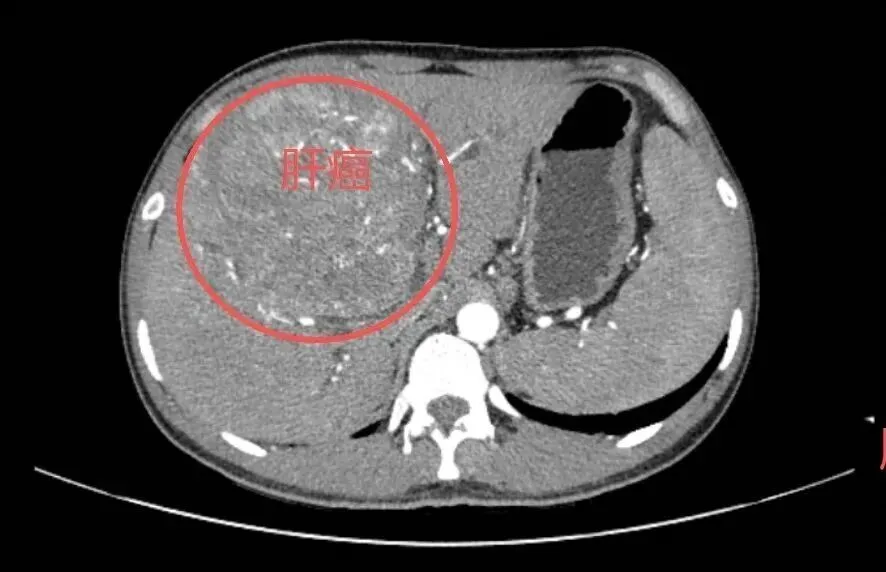

收治了一名年轻的肝癌晚期患者

25岁小王(化名)的CT检查报告上

“肝脏巨大肿瘤”等字样

让人揪心不已